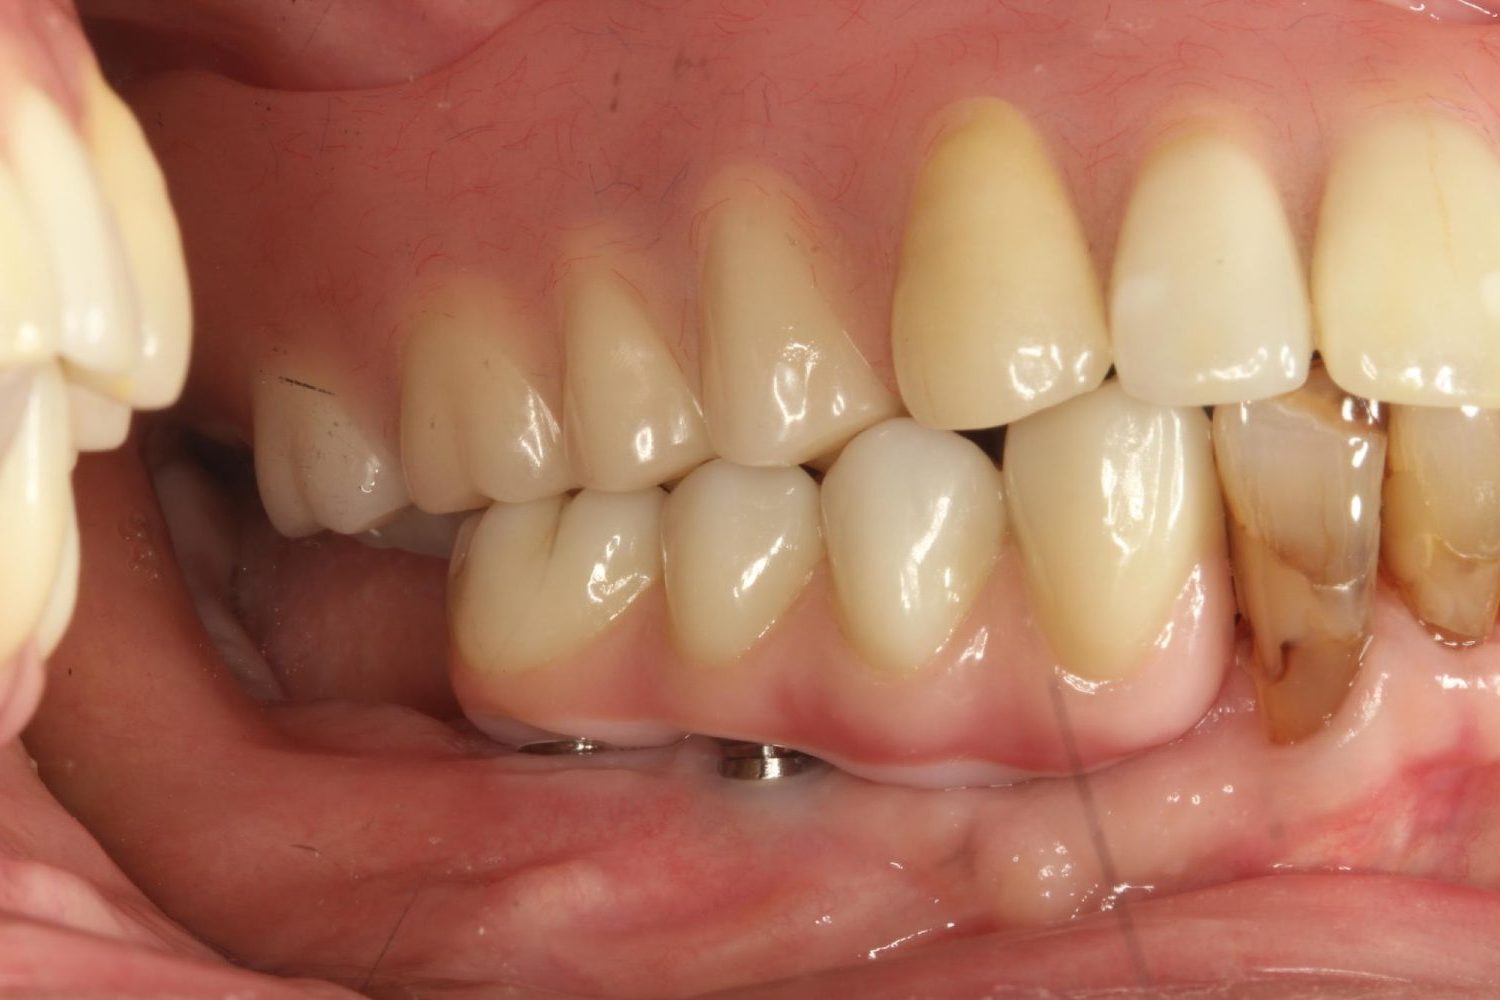

インプラント治療の症例紹介⑥

Before

After

主訴

咬めるようになりたい

治療内容

保存不可能な歯の抜歯、上下の咬み合わせを揃えて欠損部にインプラント治療

治療費

2,508,000円(税込)

治療期間

19ヶ月

通院回数

26回

想定されたリスク

※血糖値の高い方で、咬めるようになると高血糖となる可能性があるため食事制限が必要となる。インプラント周囲炎の恐れがありました。

歯の欠損による対合歯の挺出等を修正し咬合平面を揃えた症例